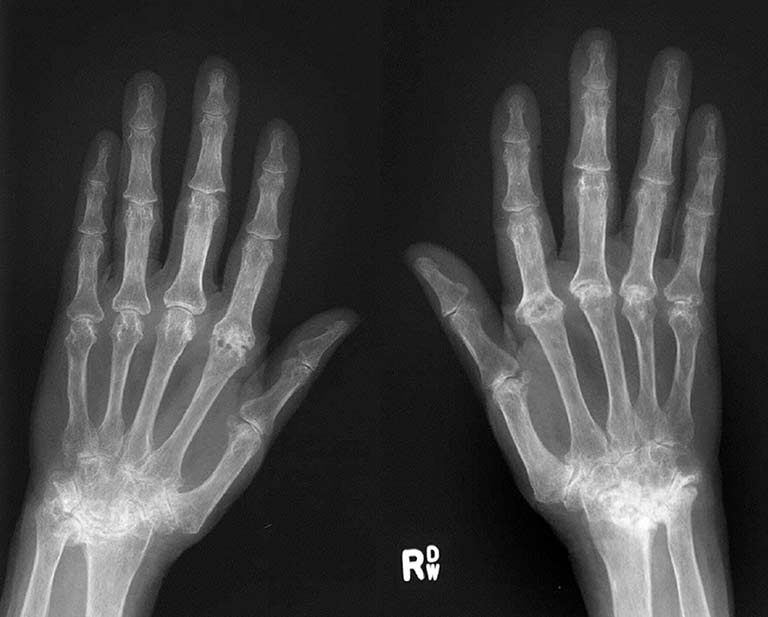

X-ray image showing mild RA, diagnosed in 1998, with no damage to finger joints by 2005

X-ray image showing severe, rapidly progressive, RA, diagnosed in 1999, with severe damage to finger joints by 2005